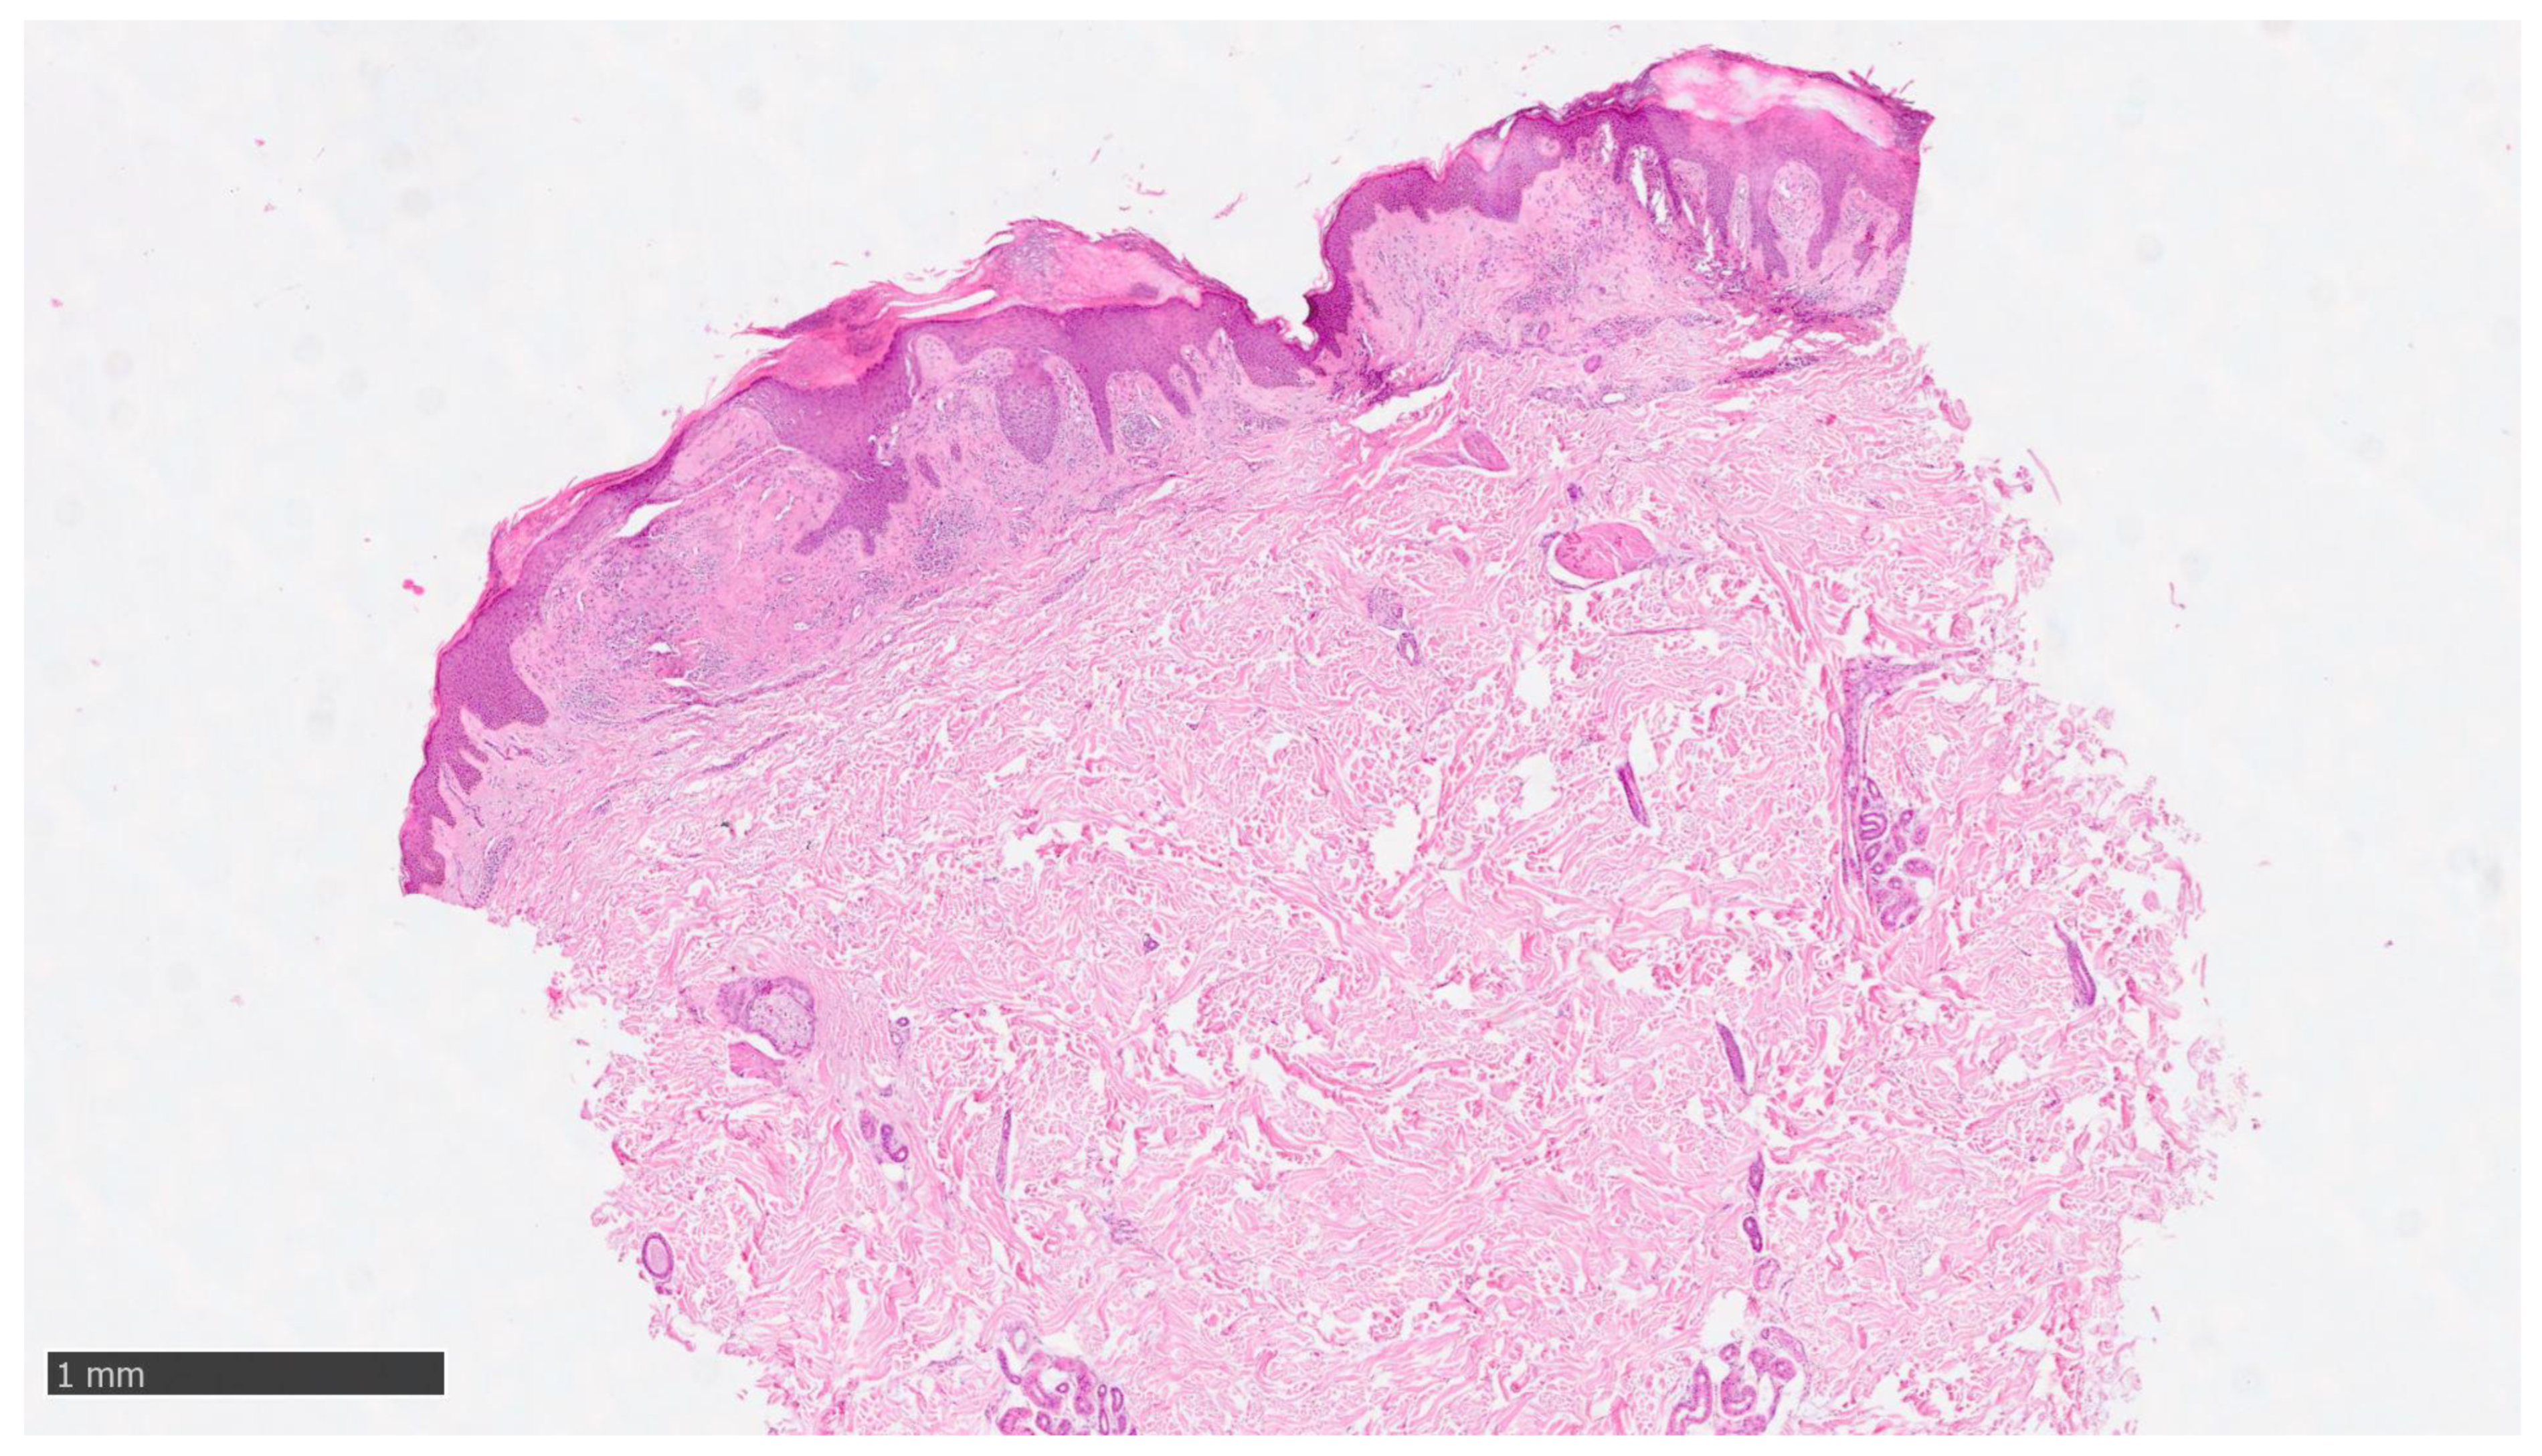

At our clinic, for a diagnosis of certainty regarding LA, an incisional biopsy was performed regarding the typical infiltrated plaques on the lower limbs. The histopathological investigations reported typical LA findings, such as the deposition of amyloid material at the papillary dermis, beneath the dermo-epidermal junction; there were also some areas with inconsistency regarding the melanic pigment and diffuse inflammatory infiltrate at the middle and superficial dermis. The epidermis was not interested in this infiltration and acts as an innocent bystander with acanthosis, hyperkeratosis, and elongation of the epidermal ridges (Figure 3, Figure 4 and Figure 5). With polarized microscopy, it was possible to appreciate the amyloid deposits beneath the dermo-epidermal junction (Figure 6).

Figure 3. Histological photomicrograph showing an area with hyperkeratosis, some degree of acanthosis, and amyloid deposition in the papillary dermis (hematoxylin–eosin, original magnification 4×).